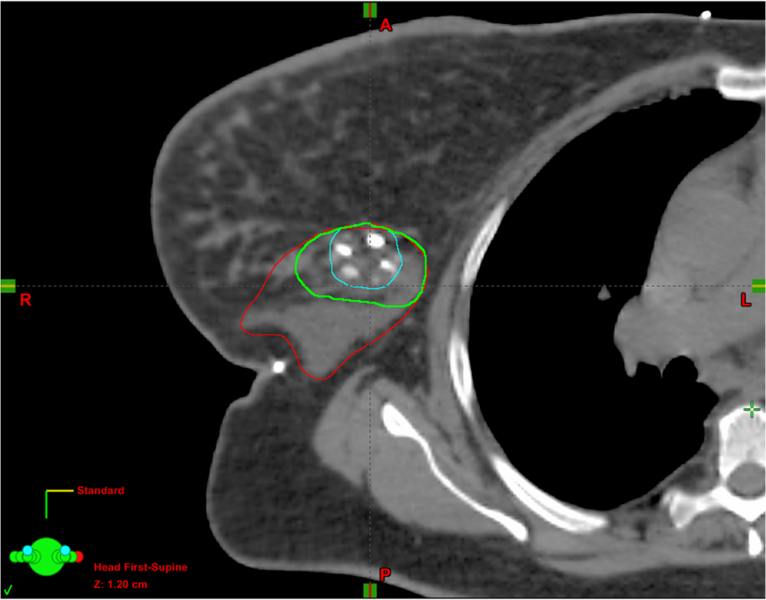

Radiation planning for breast cancer relies on accurate delineation of the post-lumpectomy target volume as identified ...

March 6, 2014 — The BioZorb 3-D surgical marker improved targeting for radiation therapy by enhancing visualization of ...